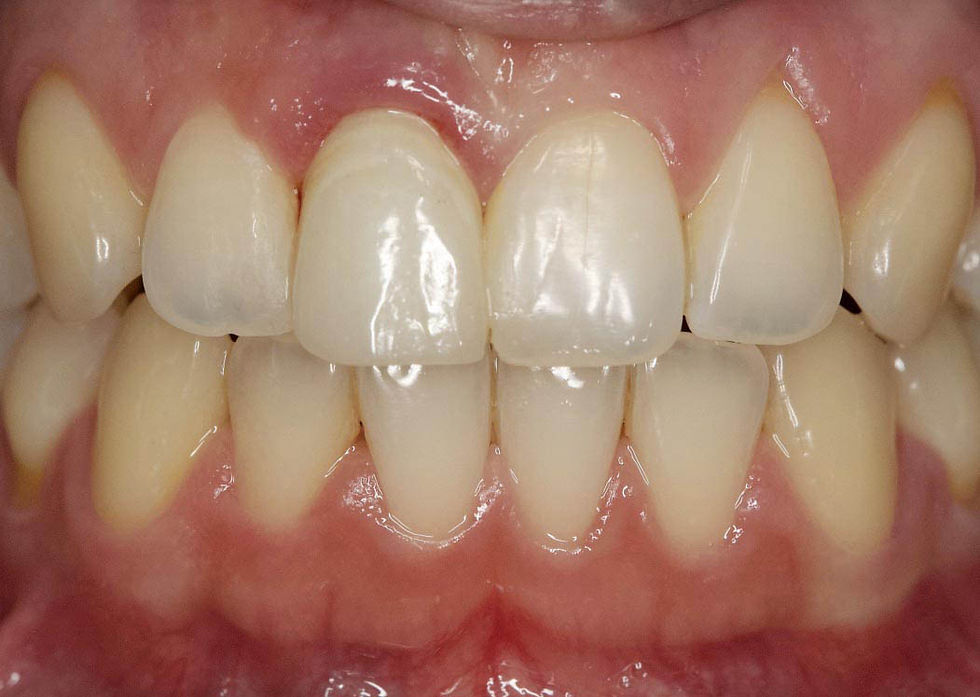

Initial clinical picture that shows an evident suffering of the free gingiva around the element 1.1.